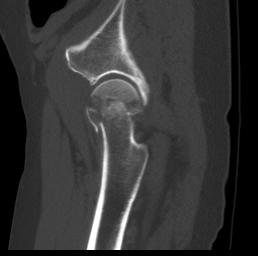

Pipkin Classification

Type I - head fracture below fovea

Type II - head fracture above fovea

Type III - Type I/II with NOF fracture

Type IV - Type I/II/III associated with acetabular fracture